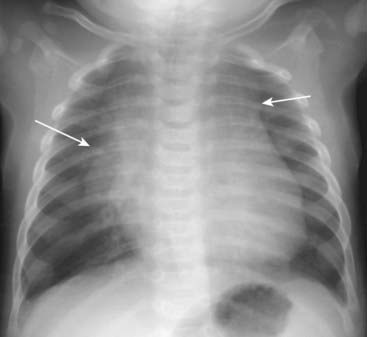

Recognizing Cardiomegaly in Infants

image Although this chapter focuses primarily on adult cardiac disease, in newborns and infants it is important to remember that the heart will normally appear larger relative to the size of the thorax than it does in adults. Whereas a cardiothoracic ratio greater than 50% is considered abnormal in adults, the cardiothoracic ratio may reach up to 65% in infants and still be normal because newborns cannot take as deep an inspiration as adults can and the relative proportions in the size of their abdomen to chest are not the same as for adults (Fig. 9-4).

image Any assessment of cardiac enlargement in an infant should take into account other factors such as the appearance of the pulmonary vasculature and any associated clinical signs or symptoms (e.g., a murmur, tachycardia, or cyanosis).

image

Figure 9-4 Normal infant chest.

In the normal infant, the cardiothoracic ratio may be as large as 65% (compared to 50% in adults) (double arrow). Any assessment of cardiac enlargement in an infant should also take into account other factors such as the appearance of the pulmonary vasculature and any associated clinical signs or symptoms (such as a murmur, tachycardia, or cyanosis).